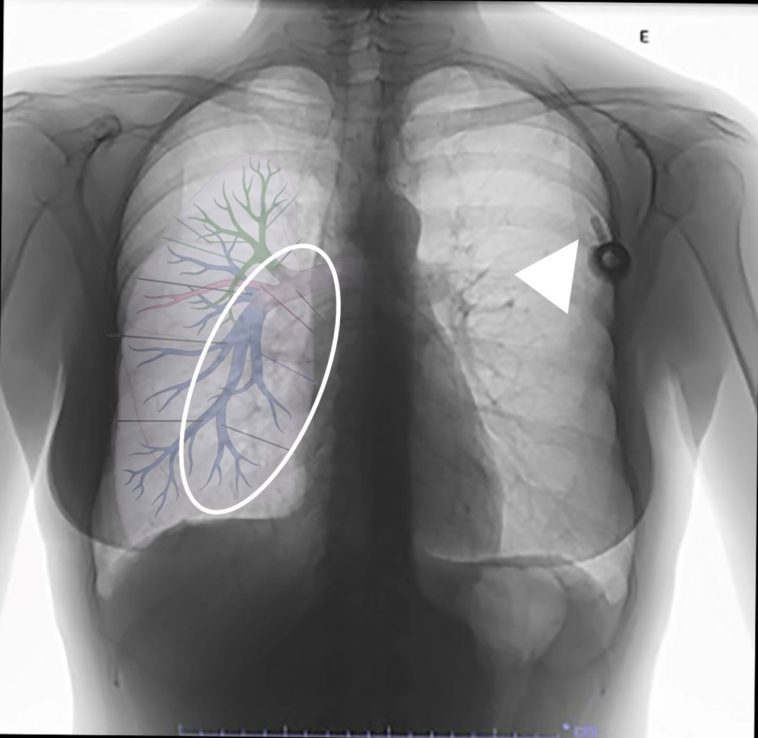

During the operation, a common iliac vein injury emerged as a result of the disc curettage process—a step that, under normal circumstances, requires precise handling and careful judgement. In an effort to control the bleeding from a small venous tear, a suction tube enhanced with a Nelaton cover was employed. This makeshift device, typically used to protect suction tips from high-speed drills, ultimately became dislodged. It then migrated through the vascular system, resulting in a pulmonary artery embolism that required immediate surgical removal by a team of thoracic surgeons.

Complications Arising from Vascular Injuries

The complications that arise from vascular injuries during lumbar surgery are not limited to severe blood loss. They can also include thromboembolic events such as deep vein thrombosis and pulmonary embolism. Some examples of related complications include:

- Hemorrhage: Significant bleeding due to vessel laceration may require rapid intervention.

- Clot Formation: When a blood vessel is compromised, there is potential for the development of clots that can migrate and cause additional issues.

- Organ Damage: In cases where emboli travel to the lungs, respiratory function can be impaired, necessitating further surgical intervention.